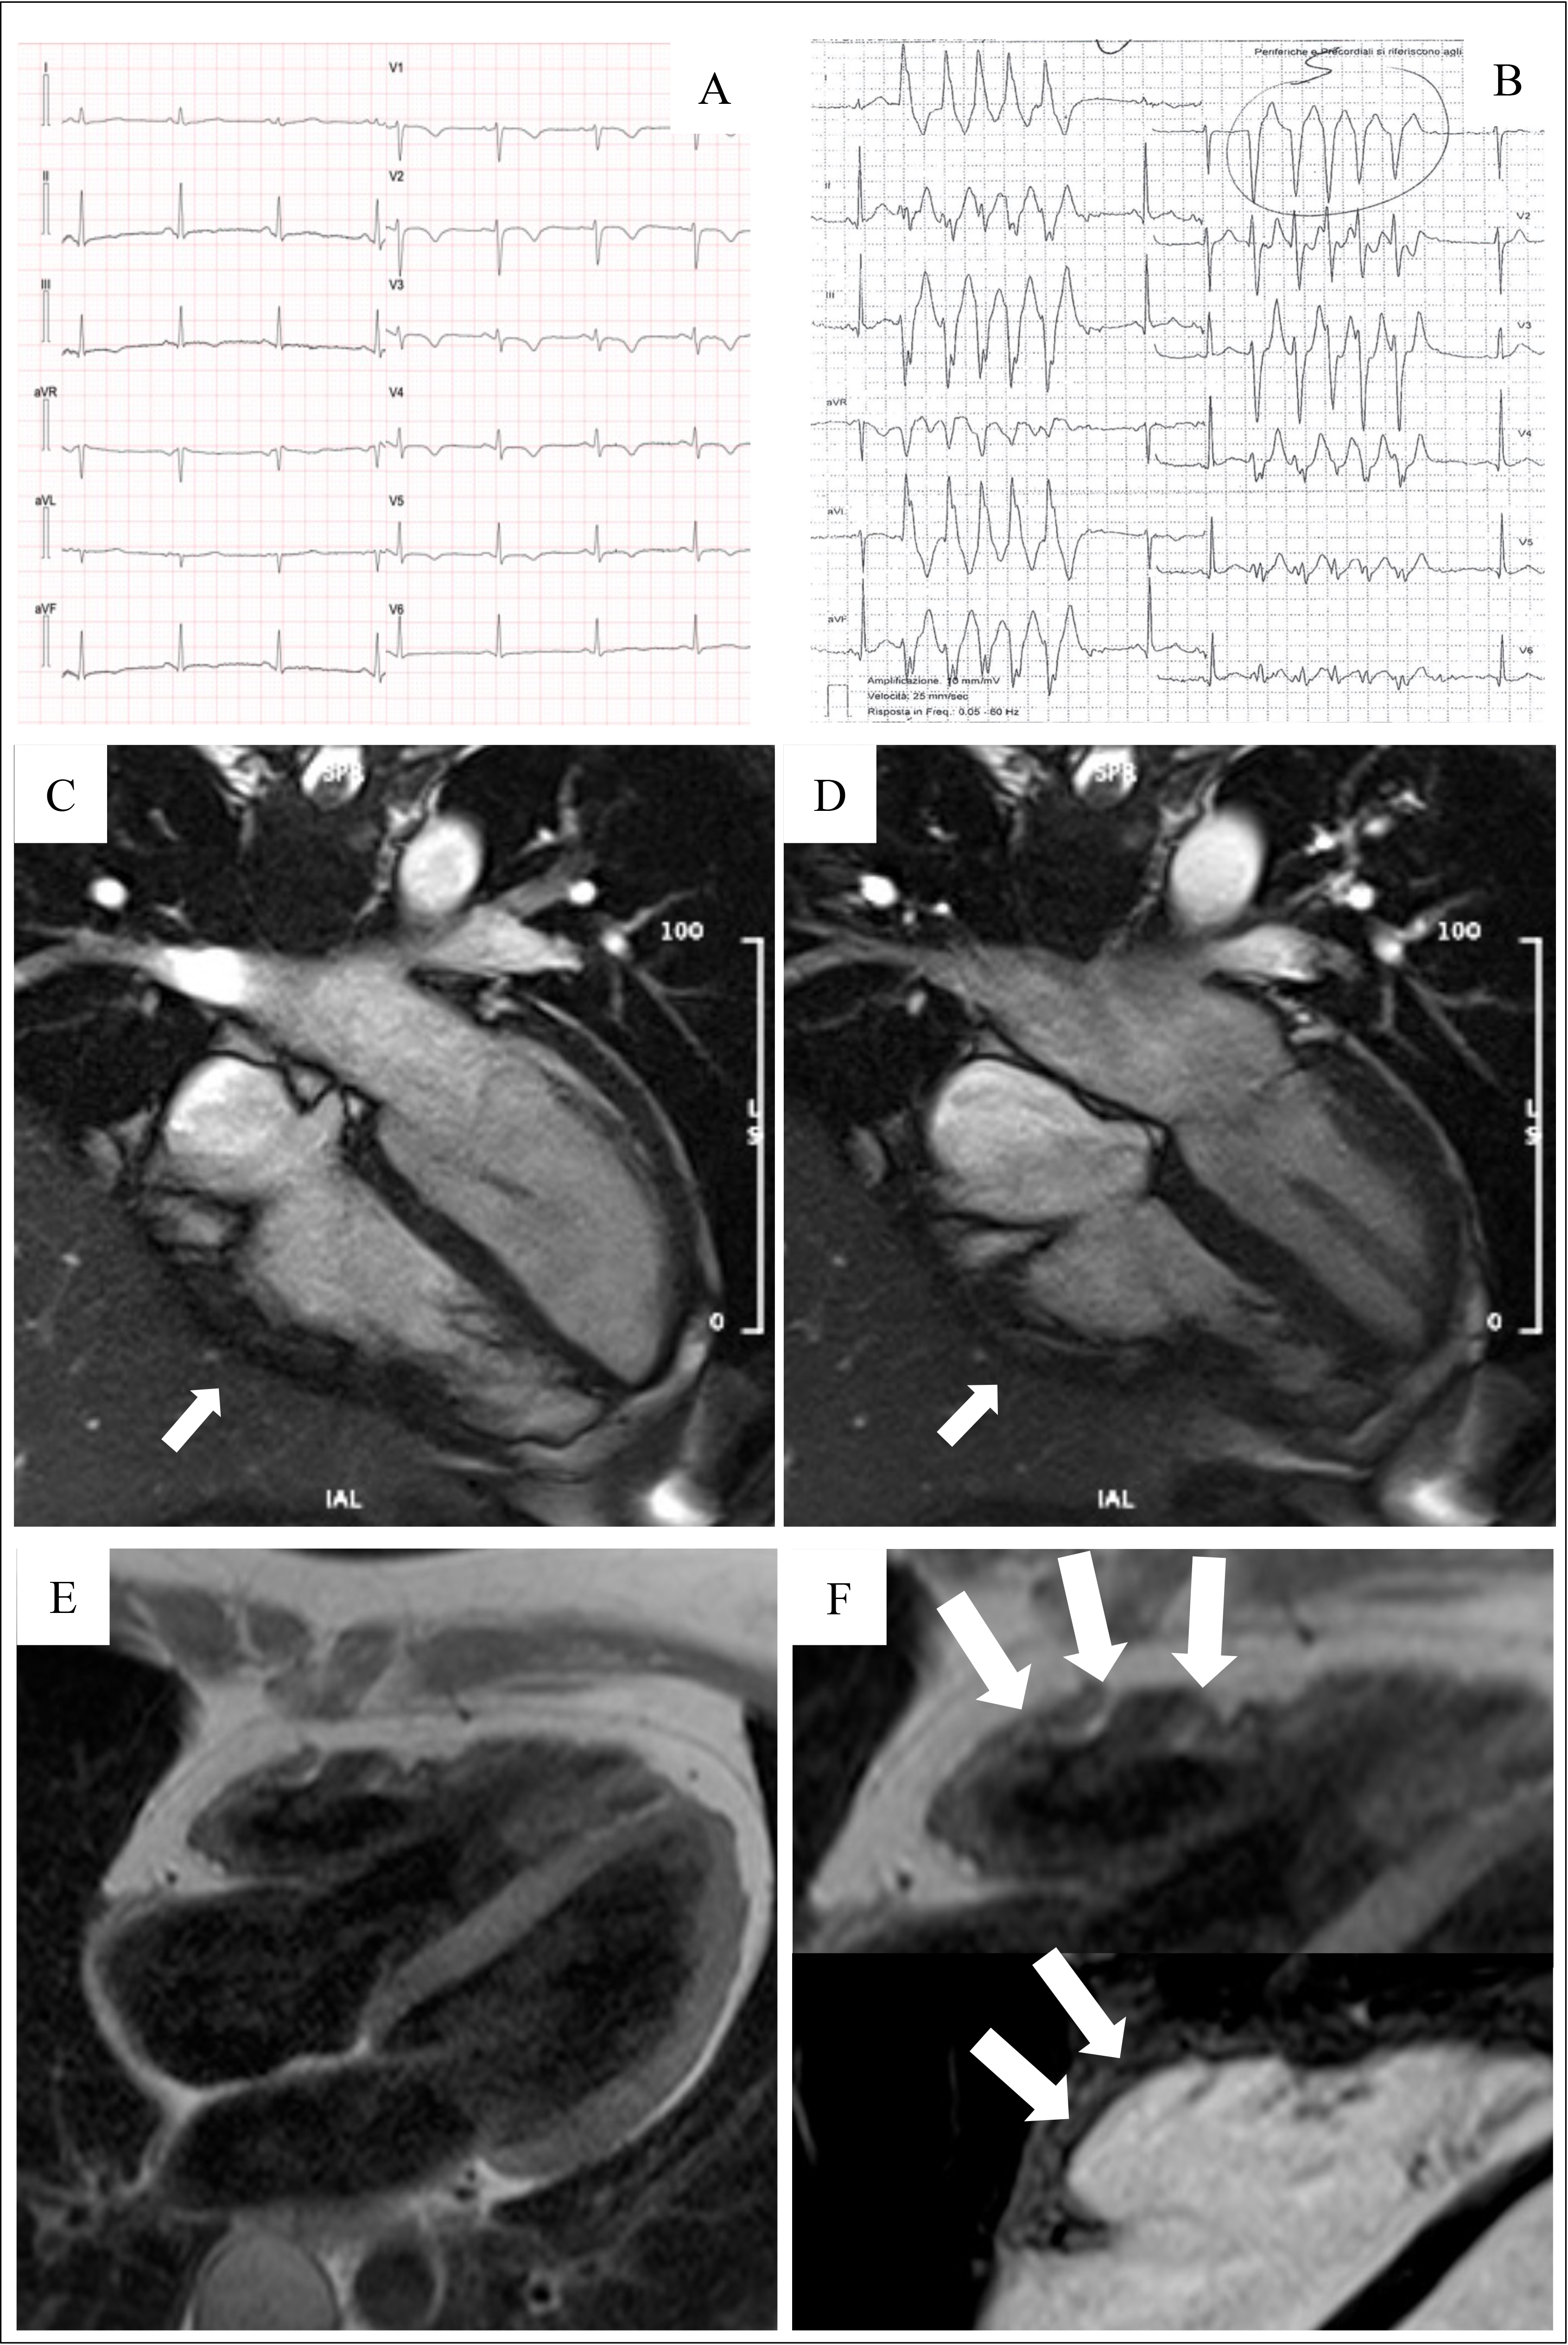

In the early stages of LV involvement, the typical non-ischemic distribution of fibro-fatty replacement sparing the subendocardial layer can explain the absence of wall motion abnormalities, dilatation, or dysfunction of the LV. Thereby, the absence of LV functional abnormalities on echo, cine-CMR or angiography cannot rule out LV involvement, and CE-CMR characterization plays a key role in detection of left-sided ACM [14, 16, 33, 34, 35, 36] (Fig. 4, Ref. [14]).

Fig. 4.Clinical and histopathological features of ALVC. Basal ECG and CMR findings in a patient who underwent cardiac transplantation because of ALVC related to a DSP gene mutation. Basal ECG revealed low QRS voltages in limb leads and flattened T-waves in infero-lateral leads (A). Post-contrast sequences on CMR (four-chamber view, B, and short-axis view, C) revealed subepicardial LGE involving the anterior septum and the whole LV free wall (“ring like” pattern) from basal to apical regions. Histology in LV inferolateral region demonstrated fibrofatty myocardial replacement in the subepicardial layer (D); a magnification of residual myocytes embedded within fibrous and fatty tissue (hematoxylin and eosin stain) (E). The diagnosis was “definite ALVC”. ALVC, arrhythmogenic left ventricular cardiomyopathy; CMR, cardiac magnetic resonance; DSP, desmoplakin gene; LGE, late gadolinium enhancement; LV, left ventricle. Adapted from Cipriani et al. [14].